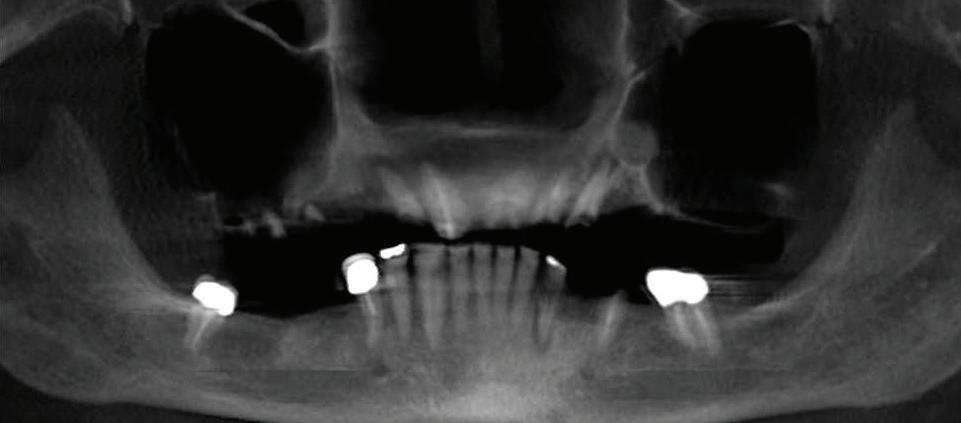

Can just four implants replace all of the teeth on the top or the bottom of your mouth? Thanks to advances in dental implant technology, that answer is a resounding yes.

Believe it or not, tooth loss is extremely common among adults, especially as we age. In fact, more than 35 million people in America are missing all of their upper and/or lower teeth. Rather than living with the discomfort and hassles of dentures, many people are opting for what is called “all-onfour” dental implant restoration.

able technique for replacing teeth, you should first understand what a dental implant is. An implant is a small titanium screw that fits inside your jawbone and replaces the root-part of a missing tooth. Minor surgery is required to insert the implants. Once the implant is in place, a crown is attached to give you a highly realistic-looking and functional prosthetic tooth.

Here’s where it gets really interesting: You do not need a dental implant for each and every one of your missing teeth. All you need is four precisely placed implants on the top of your mouth, and four on the bottom, to restore your full smile. That’s the beauty of the all-on-four. And because the implant is made of titanium, it has the unique ability to fuse to living bone and function as part of it. So eventually, the dental implant becomes part of the jawbone and serves as a strong, long-lasting foundation for your new teeth.

this bone fusion has another important benefit: it prevents future bone loss in the jaw. This helps to maintain a more youthful facial structure – and better oral health. But perhaps the biggest surprise about the all-on-four is how quickly it can transform your life.

At your All-On-Four consultation, you’ll receive a 3D CT Scan. This scan will help determine if you need implants and assist your doctors in creating your treatment plan. So if you want to learn more about dental implants, simply schedule a consultation with an All-On-Four provider. It’s the best way to find out how dental implants can change your life.